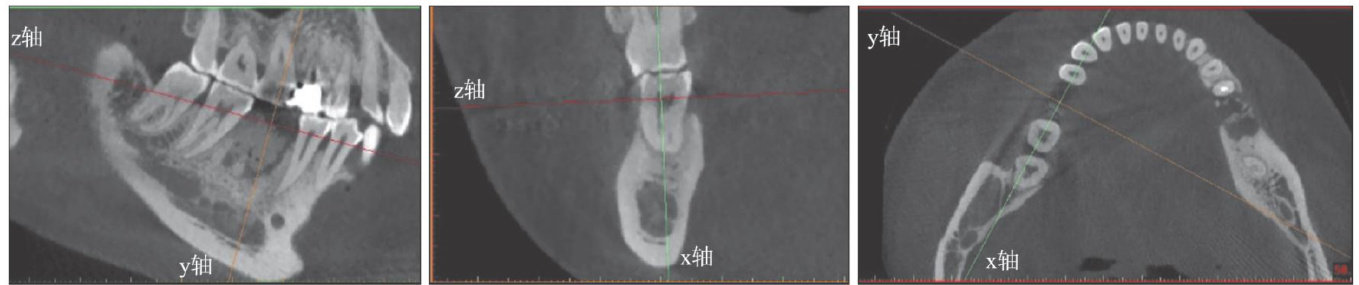

[摘要]牙吸收是在破牙细胞持续作用下发生的牙齿硬组织破坏。牙颈部外吸收是由于牙周膜或上皮下牙骨质破坏和(或)缺陷导致的牙齿颈部吸收。本文报道1例上颌中切牙外伤及正畸后牙颈部外吸收,术前通过锥形束CT充分了解患牙吸收部位和形态,术中利用显微技术及生物陶瓷和复合树脂材料分层修补对吸收部位进行严密充填修复,实现了保存患牙和尽可能长时间保存患牙健康牙髓的目标,术后6年随访效果良好。